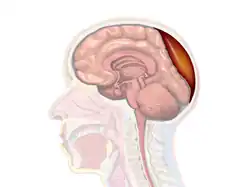

A diagram showing an epidural hematoma.

Epidural hematoma is when bleeding occurs between the tough outer membrane covering the brain (dura mater) and the skull.[4] When this condition occurs in the spinal canal, it is known as a spinal epidural hematoma.[4]

Epidural hematomas usually appear convex in shape because their expansion stops at the skull's sutures, where the dura mater is tightly attached to the skull. Thus, they expand inward toward the brain rather than along the inside of the skull, as occurs in subdural hematomas. Most people also have a skull fracture.[3]